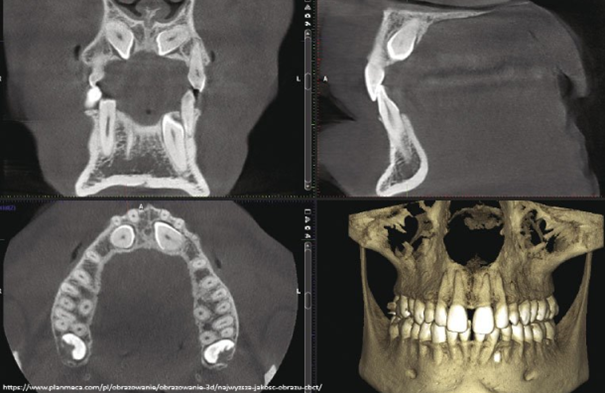

Zdjęcia fotograficzne często służą do planowania leczenia, ale są również świetnym sposobem na komunikację z pacjentem. Można na ich podstawie omówić dany problem oraz pokazać wykonaną procedurę. Zdjęcia rentgenowskie obrazują wszystko to, co jest niewidoczne gołym okiem. Stanowią bardzo ważną część w diagnostyce, leczeniu oraz monitorowaniu postępów leczniczych. Najczęściej wykonywane są zdjęcia zębowe i ortopantomograficzne. W wielu przypadkach niezbędna i niezwykle pomocna jest tomografia stożkowa (CBCT).